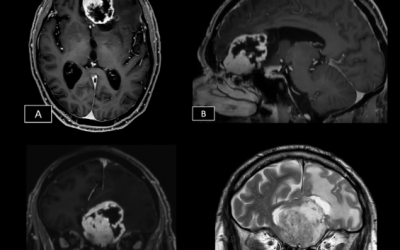

Caso del mes Febrero 2026

« Todos los casosAutores Victoria Esteban Izquierdo Enrique Marco de Lucas Hospital Universitario...